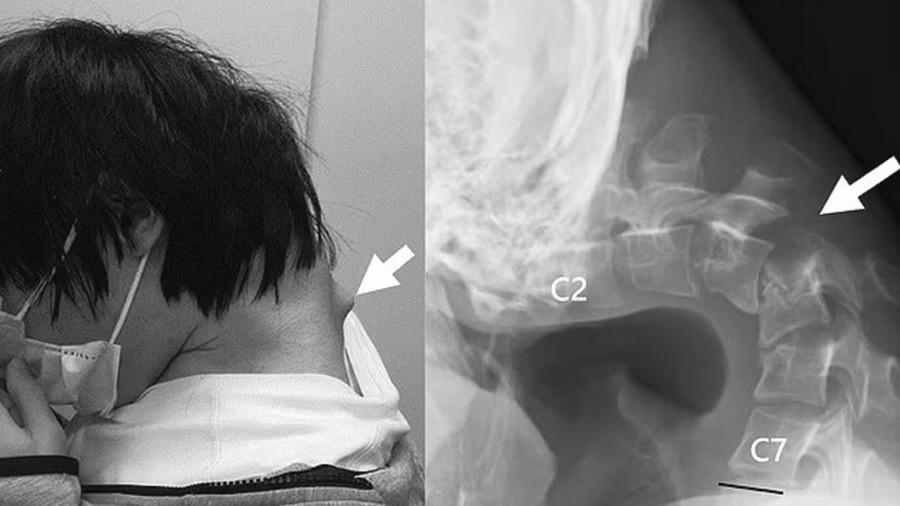

這位律師諮詢註冊脊醫,問症期間他要轉頭,都需要整個上半身一起轉,這種情況下當然很痛。在醫療床檢查後起身,他也完全做不到,要脊醫扶著他才能起床。吳慕德憶述,「若沒有人扶他,他怎樣起身呢?有一次我看到,他用手扯著自己的頭髮,借力把頭托起,才能勉強起身,但起身後已經痛到有點暈,要靜坐幾分鐘才能穿鞋站起來。」